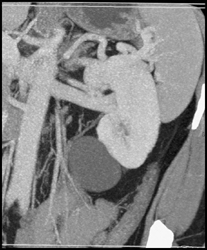

Bladder Perforation on CT Urogram